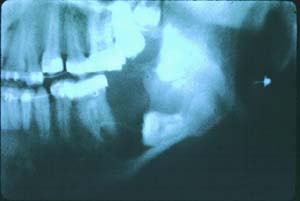

Ameloblastoma

Photo 2